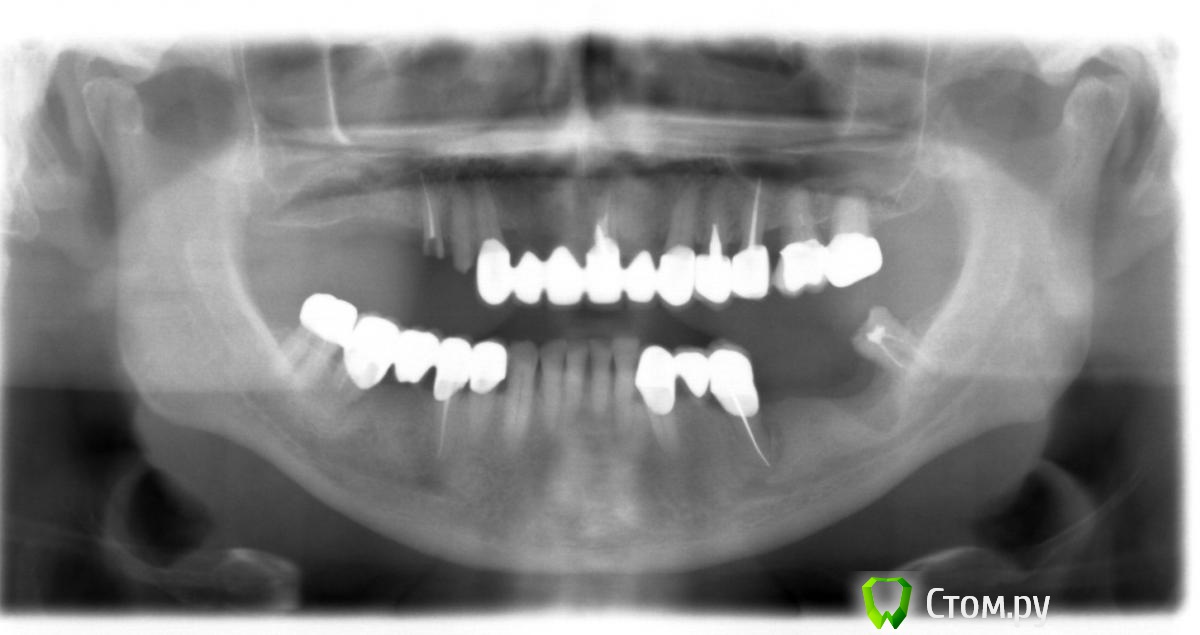

Doc Опубликовано 5 мая, 2014 Поделиться Опубликовано 5 мая, 2014 2004 год, первое посещение. 2004 год, первые имплантаты 2009 год, добавили два имплантата в область 26-27, которые по просьбе пациента были оставлены "без гарантии, пока сами не запросятся наружу", что и случилось через пять лет. Пациент претензий не имел. Сегодня утром, 5 мая 2014 года: По мне так для пациента возраста 68 лет через десять лет упорного жевания картина из серии "дай Бог каждому!". 8 Ссылка на комментарий